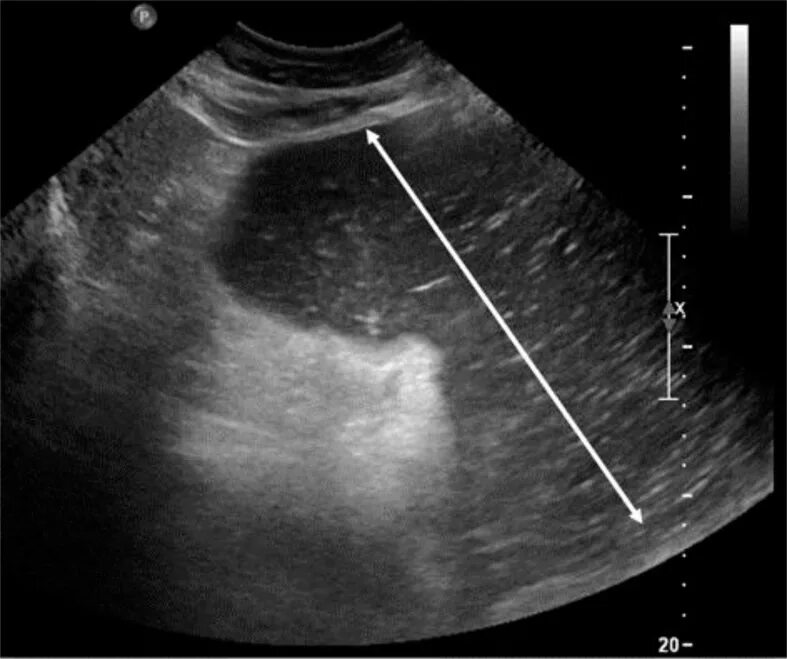

Как выглядит узи живота